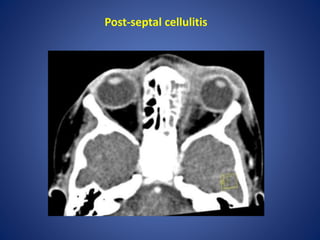

Post-septal cellulitis

Orbital and periorbitalcellulitis It is important to differentiate between orbital and periorbial cellulitis, as this has theraputic and prognostic implications: 1. peri-orbital cellulitis (pre-septal cellulitis) is limited to the soft tissues anterior to the orbital septum. This condition is often managed with oral antibiotics 2. orbital cellulitis refers to a post-septal infection (i.e. is behind or extends posterior to the orbital septum). This is a more serious condition requiring hospitalisation and parental antibiotics. Complications such as intraorbital abscess formation may require surgical intervention